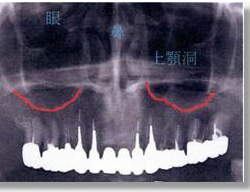

上顎洞底(上顎洞の一番底:赤線)と歯の根の先は離れており、歯による蓄膿症は起きにくい。